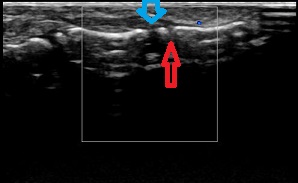

2.小学校2年生の指(赤い矢印が骨端線 青の矢印が関節)